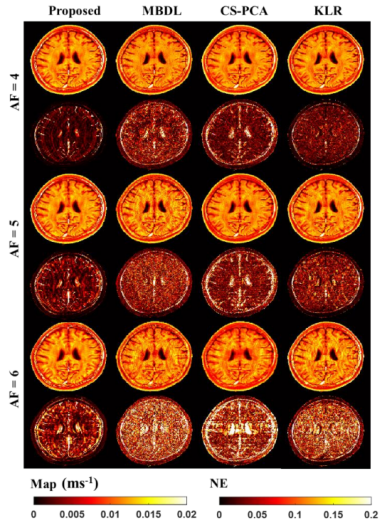

另外,研究团队最近还开展了关于快速定量磁共振参数成像的研究。在利用稀疏性加速定量磁共振参数成像的时候,由于其稀疏表示能力有限,细节混有噪声和伪影,在非线性滤波时会同时被滤除,导致加速度较大时模糊和细节丢失。针对这个问题,研究团队提出了基于非线性流形学习和正则化原像约束的快速定量磁共振参数成像算法。该方法创新性地假设待重建的图像是在高维欧几里得空间中稀疏采样的低维流形,并通过使用核函数和稀疏编码技术将图像重建问题转化为高维欧氏空间中流形结构的嵌入映射问题,最终利用正则化约束技术从高度欠采样和噪声污染的K空间数据中精确重建定量磁共振图像。这一成果率先将基于压缩感知(Compressed Sensing,CS)理论的经典快速定量磁共振参数成像方法从线性空间扩展到非线性空间,有效保护了高加速倍数下重建定量磁共振参数图像的细节特征。实验结果表明:所提出算法不仅能够提供清晰的解剖结构,而且有效地提高了在体T2定量参数图像的估计精度,为快速定量磁共振参数成像提供了一种有效的解决策略(如图3所示)。相关研究工作是与香港养和医院研究部研究主任周谊航博士开展合作,在生物医学工程领域知名期刊IEEE Transactions on Biomedical Engineering上发表题为"Accelerating MR Parameter Mapping Using Nonlinear Compressive Manifold Learning and Regularized Pre-Imaging"(DOI:10.1109/TBME.2022.3158904)的研究成果。

图3. 基于非线性流形学习和正则化原像约束的快速定量磁共振参数成像